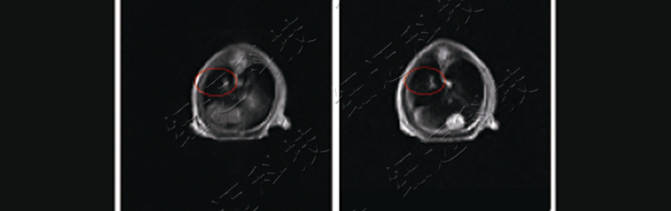

4. Tumour localisation in the lungs of nude mice